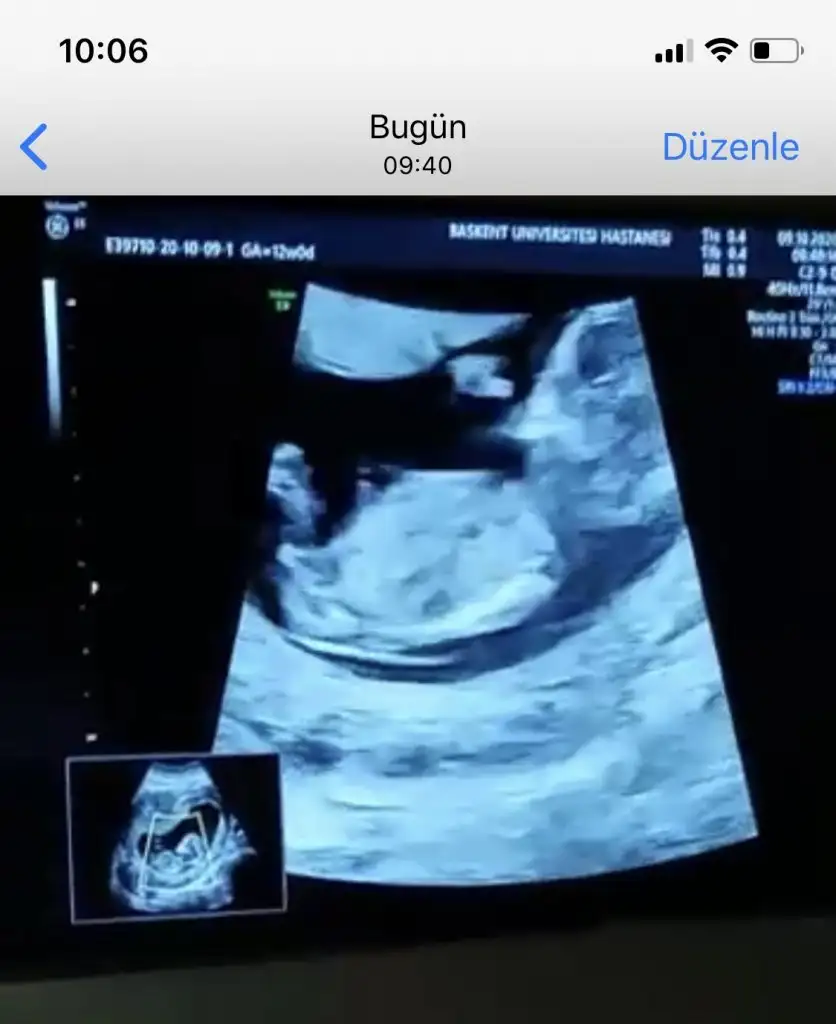

Canım bugün geldi bu ultrason doktor ölçüm de yaptı. 27 cm dedim nub açısı. O yüzden net kız da diyemem erkek de dedi. Senin yorumun nedir?Nubu çok karışık net varsa paylasin

Evet nubu karşıya bakıyor canım erkek gibi %60 ihtimal olabilirCanım bugün geldi bu ultrason doktor ölçüm de yaptı. 27 cm dedim nub açısı. O yüzden net kız da diyemem erkek de dedi. Senin yorumun nedir?

Bana bu USG paylasmadiniz ki burada karşıya bakıyor nubu %60 erkek olabilir derim bu bunlar yanitir ayrıca Dr gibi detaylı bakmıyorum Dr verdiği çıktıysa göre tahmin ediyorum ama senin bebeğin kafa şekli kizada yatkınE bu benimkiyle aynıIkra meyra cığım benim diğer görüntüme kız dedin. Bi de bu açıyı göndereyim bu ne olabilir

Kaç haftalık başka USG de paylaşın sanki kız gibi gibiRica etsem bana da bakar mısın canımIkra meyra

Kaç haftalık başka USG de paylaşın sanki kız gibi gibi

Ay dünden beri bakıyorum bakıyorum anlayamadım,açıkça anlayamıyorsak zaten kızdır kesinBana bu USG paylasmadiniz ki burada karşıya bakıyor nubu %60 erkek olabilir derim bu bunlar yanitir ayrıca Dr gibi detaylı bakmıyorum Dr verdiği çıktıysa göre tahmin ediyorum ama senin bebeğin kafa şekli kizada yatkın

Video varmi canımAy dünden beri bakıyorum bakıyorum anlayamadım,açıkça anlayamıyorsak zaten kızdır kesin30 ekimde net öğrenicez o zaman anketini de oylayacağım büyük ihtimalle kız evet, benim canım kızım